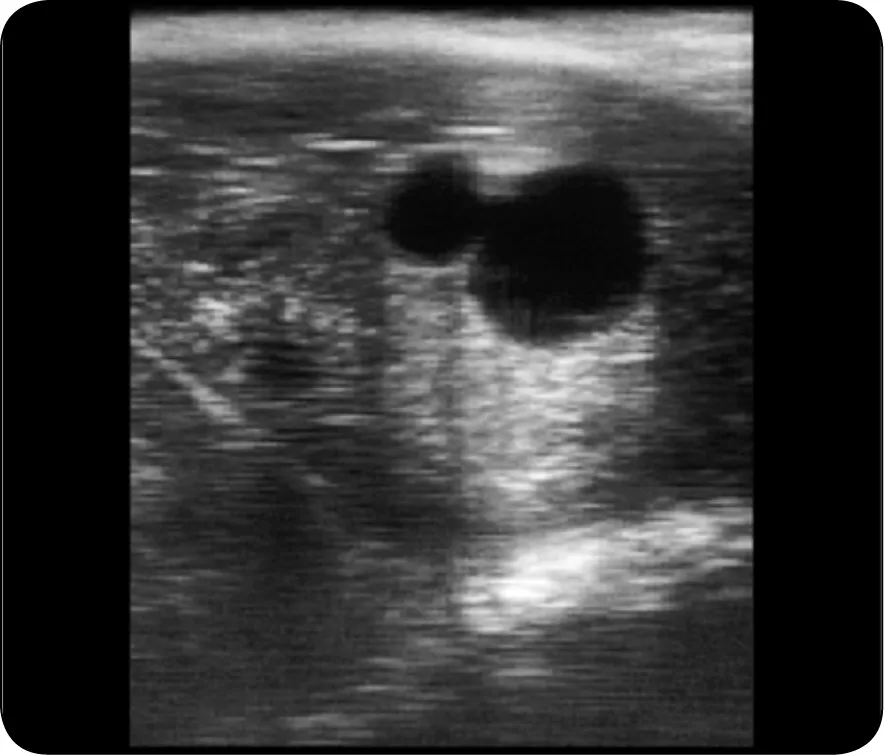

Potwierdzenie ciąży u klaczy jest kluczowe dla zapewnienia jej zdrowia oraz zdrowia przyszłego źrebaka. Badania weterynaryjne są najskuteczniejszym sposobem na potwierdzenie, że klacz jest w ciąży. Najczęściej stosowane metody to ultrasonografia oraz badanie krwi. Ultrasonografia pozwala na wizualizację zarodka już w bardzo wczesnym etapie, co daje pewność co do stanu klaczy. Z kolei badanie krwi może wykryć hormony ciążowe, co również jest miarodajnym sposobem na potwierdzenie ciąży.

Obie metody są skuteczne, ale różnią się pod względem kosztów i czasu oczekiwania na wyniki. Ultrasonografia jest bardziej kosztowna i wymaga wizyty u specjalisty, ale daje natychmiastowe rezultaty. Badanie krwi jest tańsze i można je wykonać w wielu gabinetach weterynaryjnych, ale wyniki mogą być dostępne dopiero po kilku dniach. Właściciele koni powinni rozważyć obie opcje, aby wybrać najbardziej odpowiednią dla siebie i swojego konia.